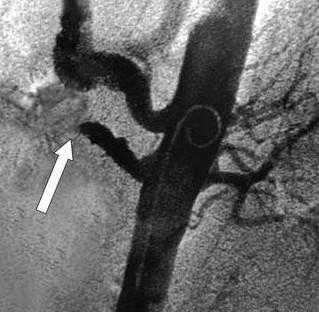

![Ангиография позволяет поставить точный диагноз и выполнить вмешательство по восстановлению кровообращения]()

Рентгеновская ангиография

Метода введения контрастного вещества непосредственно в интересующие артерии. Проводится через доступ к артериям на руке или на ноге. Позволяет прицельно изучить проходимость брыжеечных артерий и одновременно выполнить вмешательство по восстановлению проходимости закупоренной артерии. Ренгтеноангиография выступает диагностическим и лечебным методом одновременно. С помощью специальных катетеров и инструментов возможно проведение рассасывания тромбов (тромболизиса) или его удаления - тромбэктомии.

При обзорной рентгенографии брюшной полости определяется пневматизация кишечника, наличие горизонтальных уровней жидкости в брюшной полости. Специфическим методом диагностики острой окклюзии мезентериальных сосудов является селективная мезентерикография, которая уже на ранней стадии заболевания может выявить отсутствие кровотока в стволе и ветвях брыжеечной артерии. При наличии технической возможности выполняется магнитно-резонансная ангиография мезентериальных сосудов.